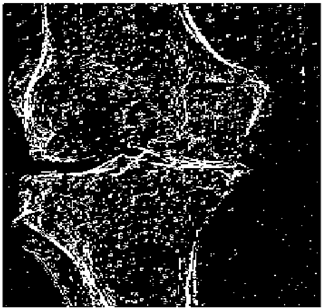

Table 10. Edge-detected image of “X-ray 1” after binarization for different noises.

NoiseCannyStandardSmooth

No noise Mathematics 10 02421 i072 Mathematics 10 02421 i073 Mathematics 10 02421 i074

G(0.001) Mathematics 10 02421 i075 Mathematics 10 02421 i076 Mathematics 10 02421 i077

G(0.002) Mathematics 10 02421 i078 Mathematics 10 02421 i079 Mathematics 10 02421 i080

G(0.003) Mathematics 10 02421 i081 Mathematics 10 02421 i082 Mathematics 10 02421 i083

I(0.25%) Mathematics 10 02421 i084 Mathematics 10 02421 i085 Mathematics 10 02421 i086

I(0.5%) Mathematics 10 02421 i087 Mathematics 10 02421 i088 Mathematics 10 02421 i089

I(1%) Mathematics 10 02421 i090 Mathematics 10 02421 i091 Mathematics 10 02421 i092

Table 10 shows the following:

• In all cases, the Canny edge detector detects more edge pixels than both fuzzy compositions.

• As the level of noise increases, Canny and standard composition become adversely affected by the noise, and still more edges are detected by Canny; however, most of the detected edges by Canny are misdetections due to the impact of noise. As is obvious from this table, the smooth composition provides a better image with reduced noise density.

• In all cases, the PFOM value for the smooth composition is always greater than the PFOM value for the standard composition, according to Table 6.